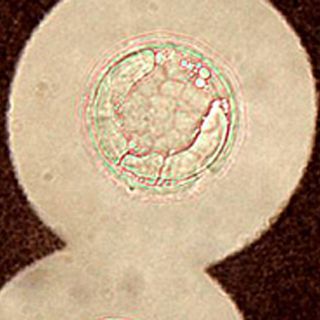

MADRID, ESPAÑA (27/JUN/2010).- Muchos tenemos en los pulmones un hongo ambiental que emplea una táctica para burlar las defensas y permanecer con vida, generando una infección puede aumentar su tamaño hasta mil veces, y lo convierte en invulnerable a los ataques del sistema inmune.

El hongo, denominado 'Cryptococcus neoformans', es una levadura que se encuentra en el aire por todo el mundo y se ha descrito por primera vez su mecanismo de supervivencia que podría ser también la estrategia seguida por otros agentes infecciosos.